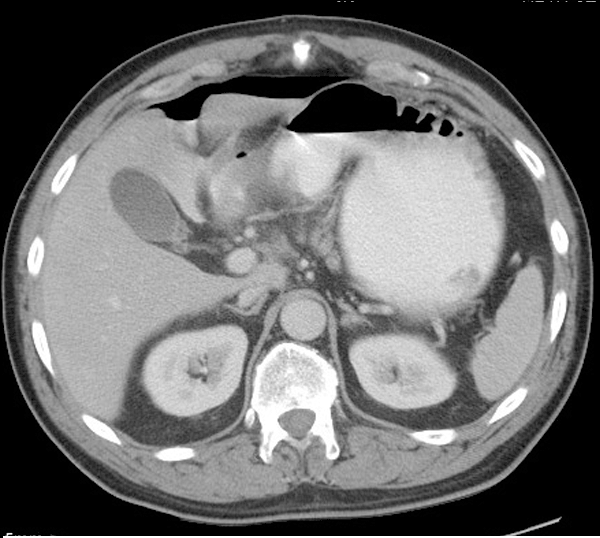

Image radiologique TDM normale de l'intestin :

Il y avait la difference de

image de intestin grele avec gros intestin ( colon )

en coupe TDM axiale . Intestin grele sont en pleine

du contenue , avec plusieure des plies muqueuse . La

colon avait moindre de plie muqueuse et sa diametre est grande et parfois presente

de poche a air . |

Images normales

de intestin grele en coupe sagitale .( Click

pour ouvrir agrandissement ) |